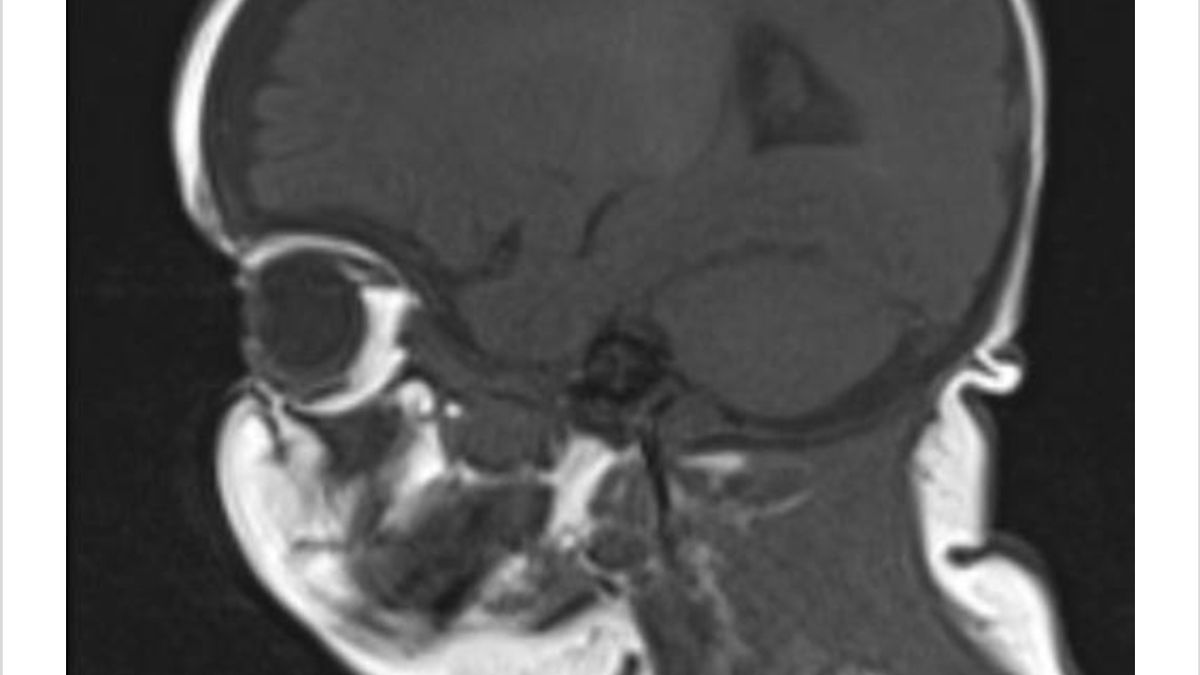

Inicio sesión y veo las imágenes. Imágenes que naturalmente no puedo entender. También hay un informe. Abro el informe y me abruma con términos médicos difíciles y frases que ni siquiera parecen holandesas. Reconozco algunas palabras: “anormal”, “agrandado” y “quiste”.Dios mío. Así que después de todo sí encontraron algo.

El pequeño Marco tiene algo en su cabeza que realmente no debería estar allí. Mi mente está completamente cortocircuitada. Salgo afuera. Aún sin saber a dónde ir o qué quiero lograr, pero ya no soporto estar en casa. Eventualmente, camino hacia la casa de un amigo cercano para tomar aire. Allí, decido enviar el informe lleno de lenguaje complicado a una amiga, que también es enfermera. Ella traduce el documento para nosotros a términos comprensibles para el lego. Horrible. Esta será sin duda la noche más larga de nuestras vidas. No recibiremos una llamada del pediatra hasta mañana para escuchar su perspectiva sobre los hechos. Decido mantener a Marco cerca de mí esta noche.

La mañana en realidad pasa volando. Nuestro Lewis no se siente bien y está vomitando por todas partes. Es bueno que se quede en casa conmigo. La distracción perfecta. A las 8.30 am llamo yo mismo al horario de atención de mi pediatra. Ella dice que miró las imágenes anoche. Ya está en contacto con un neurólogo pediátrico en el hospital especializado para consultar. Tienen una reunión telefónica programada y ella me devolverá la llamada después. A las 9.30 am recibimos la llamada. Debemos conducir al hospital inmediatamente. Hay una masa desconocida en la cabeza de Marco en un lugar donde no se supone que haya nada. No nos dan más información. El neurólogo pediátrico nos espera en el hospital. Quieren monitorear a Marco 24/7.

El siguiente médico proporciona aclaraciones sobre dónde estamos: oncología. Solo la palabra ya me hace llorar. Dice que este es el procedimiento cuando encuentran un tumor. Los médicos aún no saben si es benigno o maligno. El suelo se desvanece bajo mis pies. Ingresado en 'oncología', mi hijo. Esa tarde nos vemos abrumados por pediatras, neurólogos pediátricos, oncólogos pediátricos, un neurocirujano y un oftalmólogo. Cada vez tenemos que contar nuestra historia y nuestros hallazgos de nuevo. Aclaran un poco cada vez lo que ven y lo que podría o sucederá.

Poco a poco, aprenderemos más. Por ahora, solo sabemos que estamos en el hospital y debemos permanecer allí durante varios días. También sabemos que Marco tendrá que someterse a muchas pruebas. Ya sabemos que hay un tumor presionando su tronco encefálico. Aprendemos que el tronco encefálico controla todo nuestro cuerpo, incluyendo nuestra respiración y nuestro corazón. Marco tiene que ser monitoreado las 24 horas del día, los 7 días de la semana. No quieren correr el riesgo de que la presión en el tronco encefálico sea demasiado grande y tenga problemas en casa. También sabemos que se tendrá que realizar una nueva tomografía cerebral con líquido de contraste. Y que los cirujanos pueden querer tomar una biopsia. Además, permaneceremos en la incertidumbre por un tiempo.